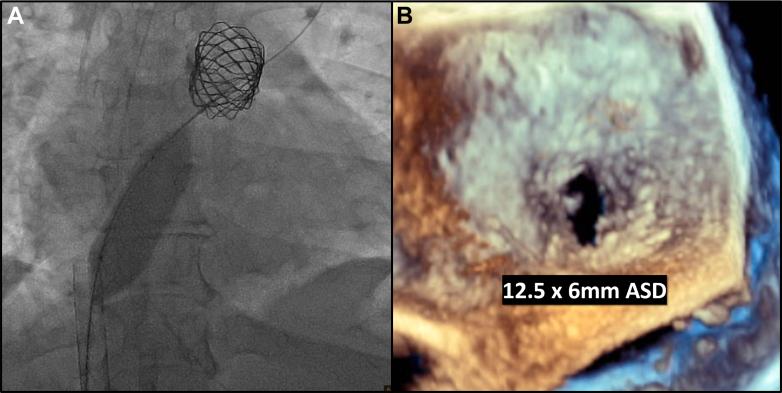

A 33-year-old woman with aortic valve stenosis status-post Ross at age 6 years developed symptomatic right heart failure from right ventricle to pulmonary artery conduit stenosis. Conduit rehabilitation and transcatheter pulmonary valve replacement resulted in acute left atrial hypertension and respiratory failure requiring venoarterial extracorporeal membrane oxygenation and atrial septal defect creation as a bridge to recovery.

一名33岁女性,6岁时接受Ross手术治疗主动脉瓣狭窄,现因右心室至肺动脉管道狭窄出现症状性右心衰竭。管道修复及经导管肺动脉瓣置换术后导致急性左房高压和呼吸衰竭,需要进行静脉-动脉体外膜肺氧合,并创建房间隔缺损作为恢复的桥梁。